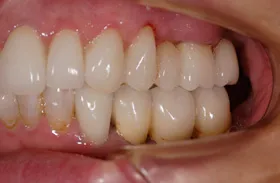

歯が割れた為来院されたケース

■治療前

■治療後

治療のポイント

- 右上奥の骨 → 骨をつくりました

- 前歯を支える歯茎 → 歯茎の幅をつくりました

- 左下奥の歯肉 → 歯肉を移植しました

骨が深く欠損していた箇所は骨を作り、歯茎が薄くなっていた箇所は増大させました。

また左下奥インプラントを支える歯茎が柔らかく、歯磨きが困難な為、歯肉を移植し丈夫な歯茎にしました。

| 主訴 | 上顎の前歯が割れて噛むことができない |

|---|---|

| 治療方法 | かみ合わせが低くなり、下の歯が上の歯に対して、突き上げていたのでかみ合わせの高さを修正し突き上げをなくした |

| 治療期間 | 約2年 |

| 通院回数等 | 40回 |

| 費用 | 5,500,000円(税込) |

| リスク・副作用 | 外科的に骨を作る為、治療後に腫れることがある |